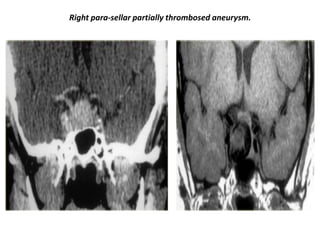

Right para-sellar partially thrombosed aneurysm.

Aneurysm of right para-sellar region with partially thrombosed aneurysm.

Enhanced and non-enhanced study of right para-sellar aneurysm.